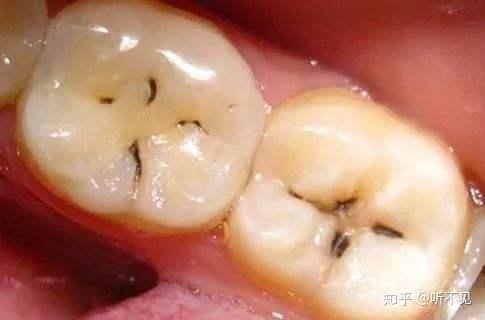

一、龋齿

就是我们常说的虫牙、蛀牙。此时牙齿不仅有颜色的改变,还会发现龋坏的牙体组织被腐蚀,变软,甚至出现黑洞,进而发生食物嵌塞,牙疼的现象。

此时需要请牙科医生进行治疗。